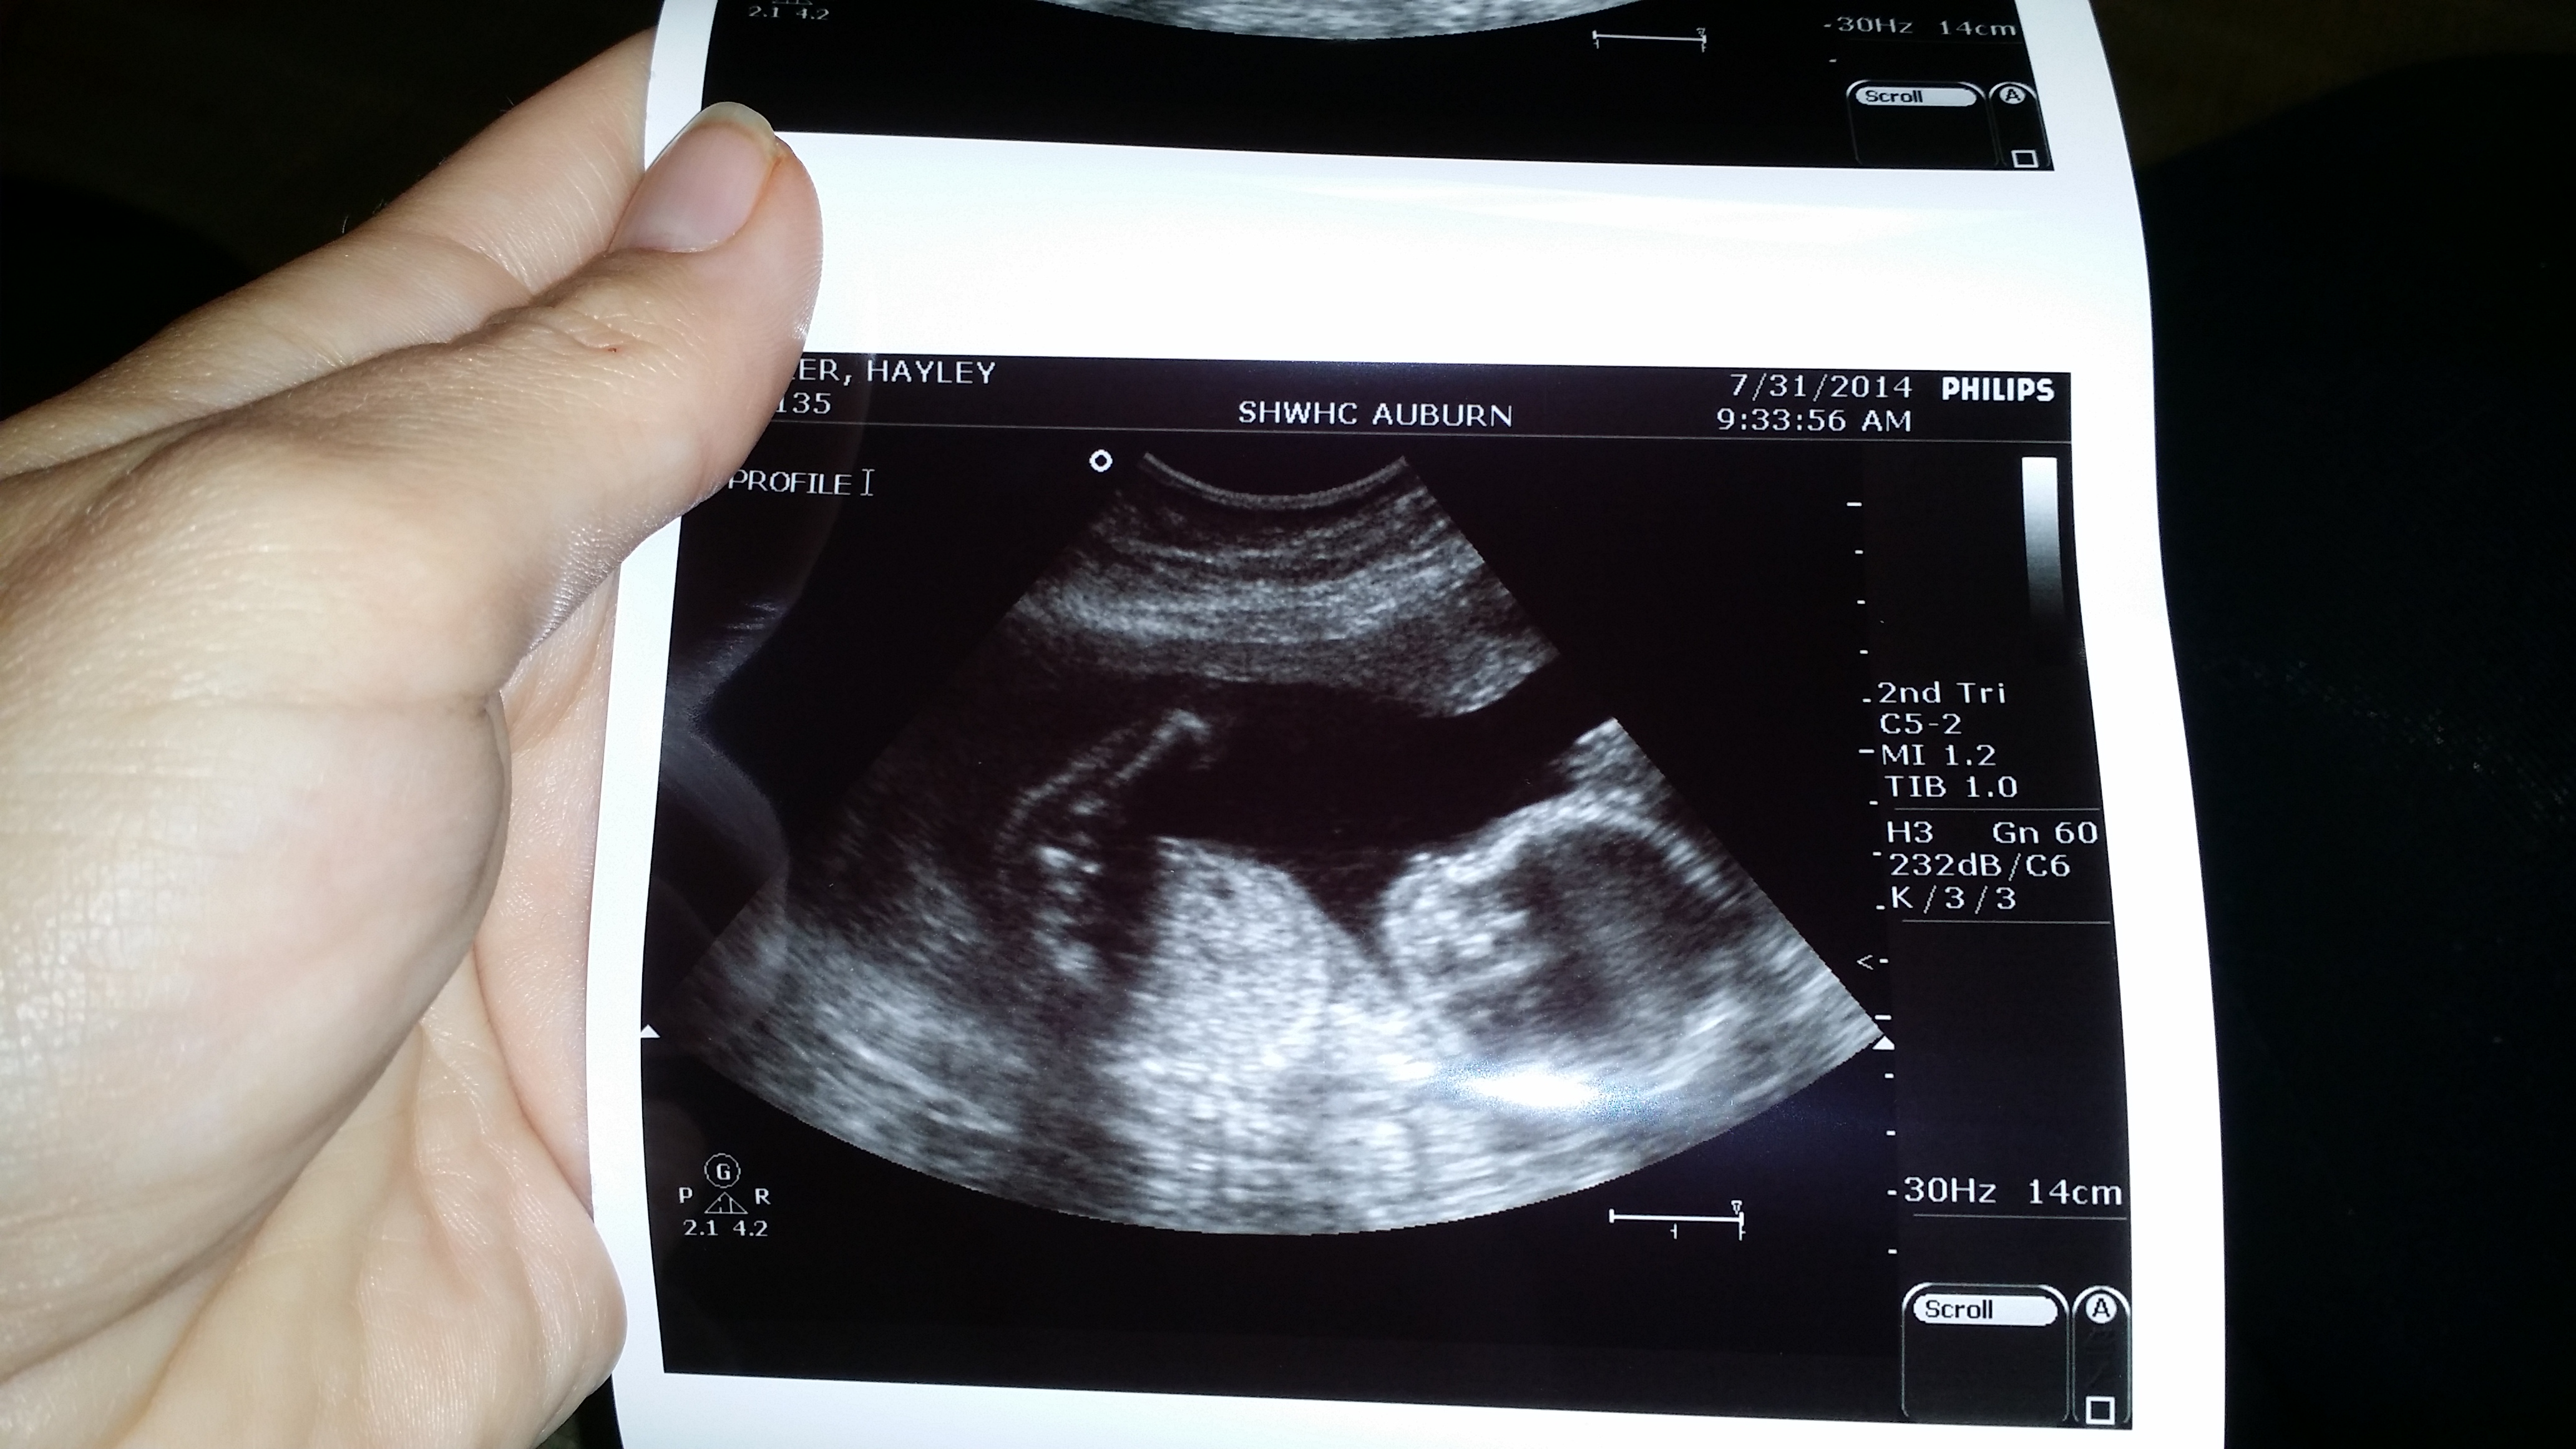

We're staying Team Green, but I definitely saw the hamburger buns while the tech was measuring the thigh bones... keeping my mouth shut b/c I know it would break SO's heart if the surprise was spoiled.

Little one weighs in at 13oz (decent size for 20w2d) and everything looked perfect! They also checked my cervix and it's holding steady at 3.4cm, so a great measurement. Heartbeat was 145. Next appointment is in 4 weeks!